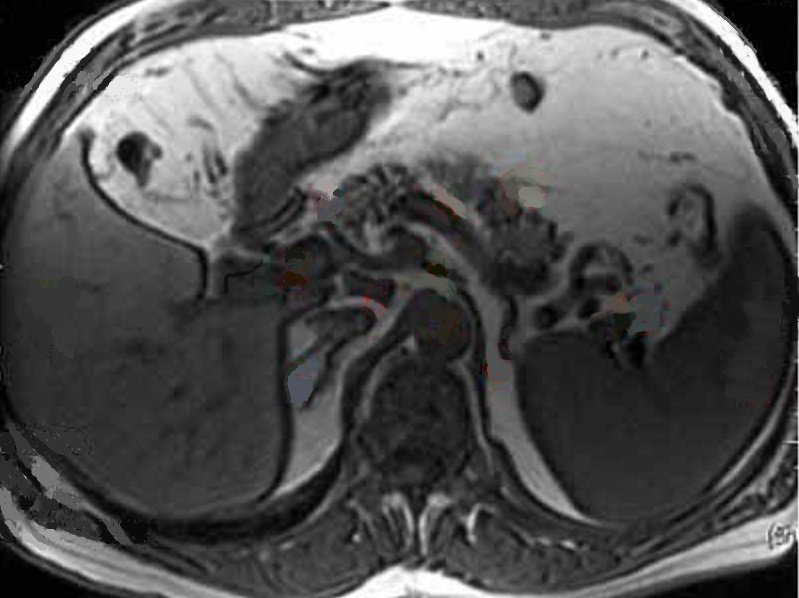

Image

radiologique IRM ponderee T1 de la rate avec aspect

parenchymateuse homogene et leregemant moins

intensite que le foie |

Aspect radiologique IRM de

la rate pondere sur T2 FatSat . La parenchyme de la

rate est homogène et tres hypersignal que le foie et

les autres organes . Image IRM T2 FATSAT coupe axial |